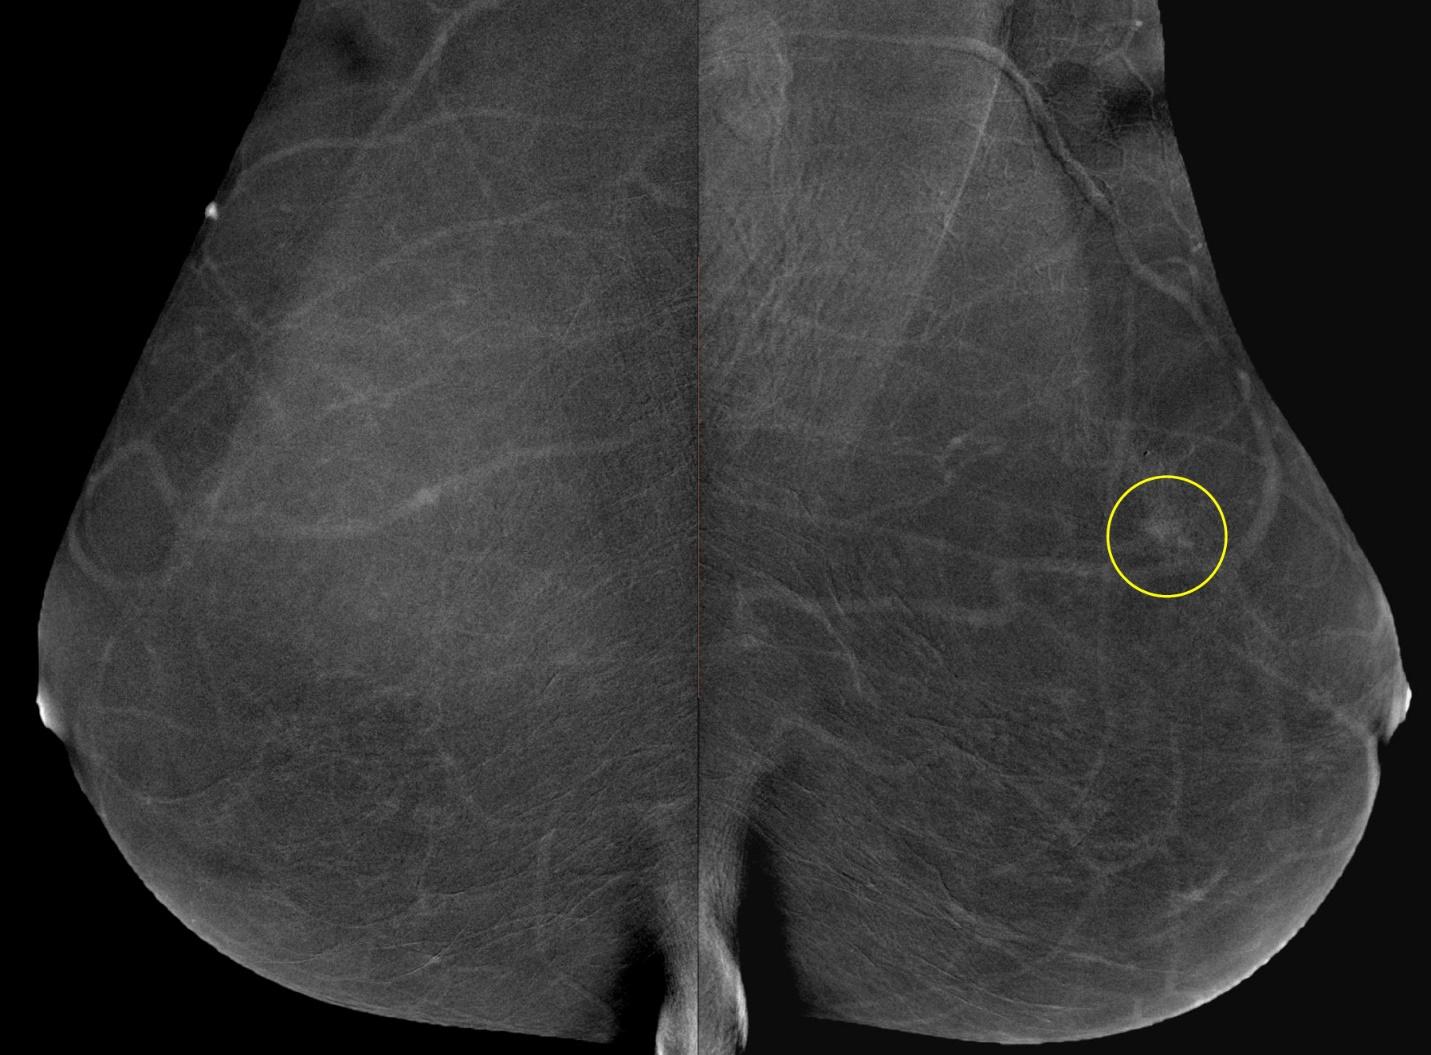

Шаг 8. Нужна ли функция цифрового томосинтеза (DBT)?

Шаг 9. Нужна ли функция контрастной спектральной двуэнергетической маммографии (CESM)?